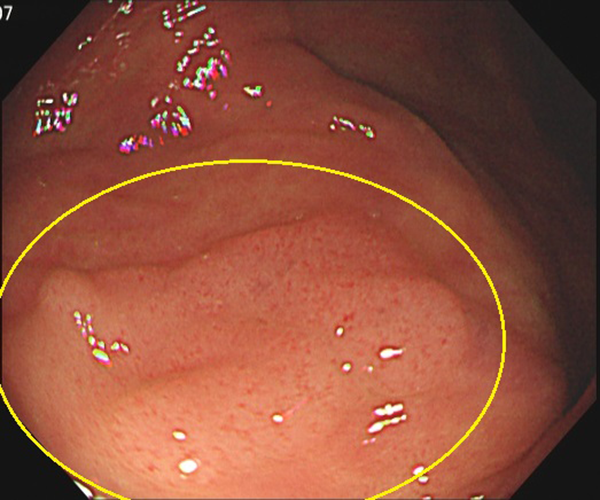

⑤大腸がん(側方発育型腫瘍(LST))

1. 大腸ポリープ既往歴があり、定期的検査として内視鏡検査を施行、横行結腸に10mm強の表面比較的平滑な扁平隆起を認めます。

2. NBI画像処理で表面構造の異常(周辺が均一な小円形構造に対し、不均一)を認めます。側方発育型腫瘍(非顆粒型)であり内視鏡的粘膜切除術で治癒、粘膜内癌と診断されました。